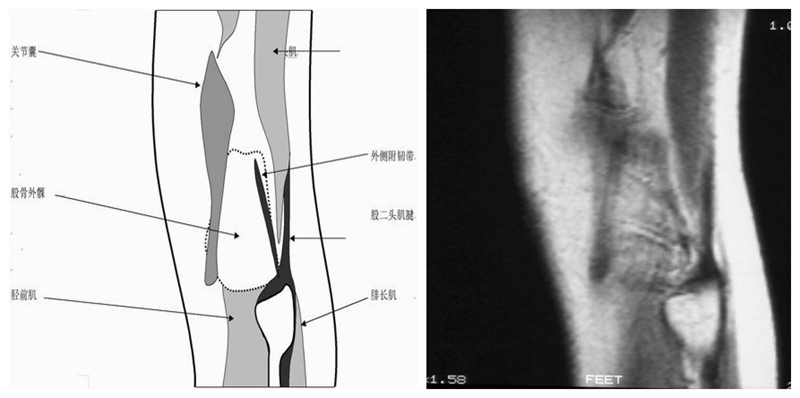

矢状位解剖第七层

矢状位解剖第八层